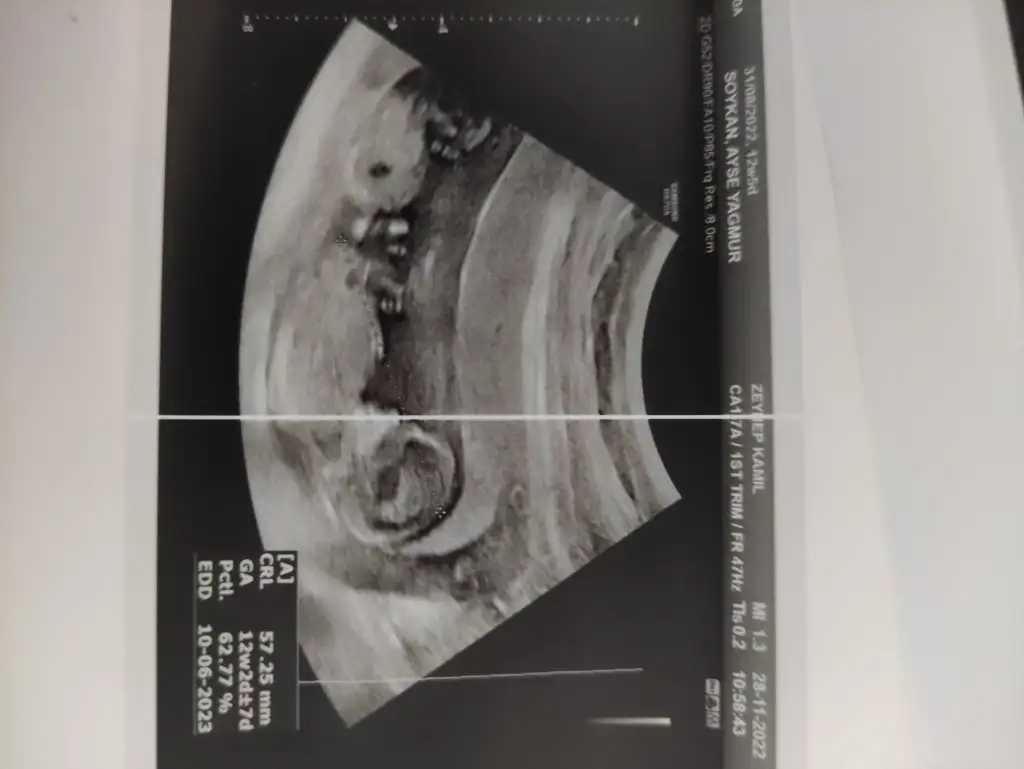

Allah tamamına erdirsin inşallah daha net foto varsa atarmısın ayrıca crl de yazar onu da çekersen tahminde bulunabilecemRica etsek bize de bi yorum gelir miburda 12 hafta 3 günlük. Doktor hiç tahminde bulunmadı

Kaç haftalık canım ayrıca crl de nuba göre bakacamEki Görüntüle 3171897 biz de tahminleri alabilir miyiz

Ay canım benim kıza benzetim Allah tamamına erdirsinEki Görüntüle 3172524 ben de minik bi tahmin alabilir miyim13+3 günlük